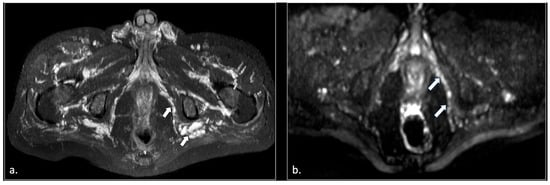

MRI in Chronic Pudendal Neuralgia: Diagnostic Criteria and Associated Pathologies

by Michele Gaeta, Sofia Turturici, Karol Galletta, Carmelo Geremia, Attilio Tuscano, Aurelio Gaeta, Marco Cavallaro, Salvatore Silipigni and Francesca Granata

Diagnostics 2026, 16(2), 326; https://doi.org/10.3390/diagnostics16020326 (registering DOI) - 20 Jan 2026

Background/Objectives: Chronic pudendal neuralgia is a relatively rare condition in the general population, with an incidence of 1%. Although diagnosis of pudendal neuralgia is mainly clinical, Magnetic Resonance Imaging (MRI) is commonly performed to obtain further information. However, clear criteria and guidelines for MRI diagnosis and the clinical–radiological correlation are still not definite. Methods: We reviewed 81 patients with chronic pudendal neuralgia, studied by an MRI designed protocol for a pelvis and pelvic floor examination. A key element of the protocol was the use of a diffusion-weighted imaging (DWI) technique with echo planar imaging (EPI) sequence (b-values of 0, 100, and 600) for the neurographic evaluation of the nerve. Results: MRI examination revealed DWI abnormalities in 42/81 patients. Pudendal nerve abnormalities were unilateral in 33/42 patients and bilateral in 9/42. Moreover, in 23/42 patients, pathologies related to a high probability of neuropathy have been identified. Conclusions: This study highlights the role of pelvic MRI as a valuable imaging modality in the evaluation of patients with chronic pudendal neuralgia. In the study protocol we propose, an essential role is played by the DWI technique, which improves the visual definition of the pudendal nerve and related anatomical structures. By focusing on anatomical visualization and structured image interpretation, our work provides a practical imaging-oriented contribution to a field in which standardized MRI evaluation is still lacking. Full article